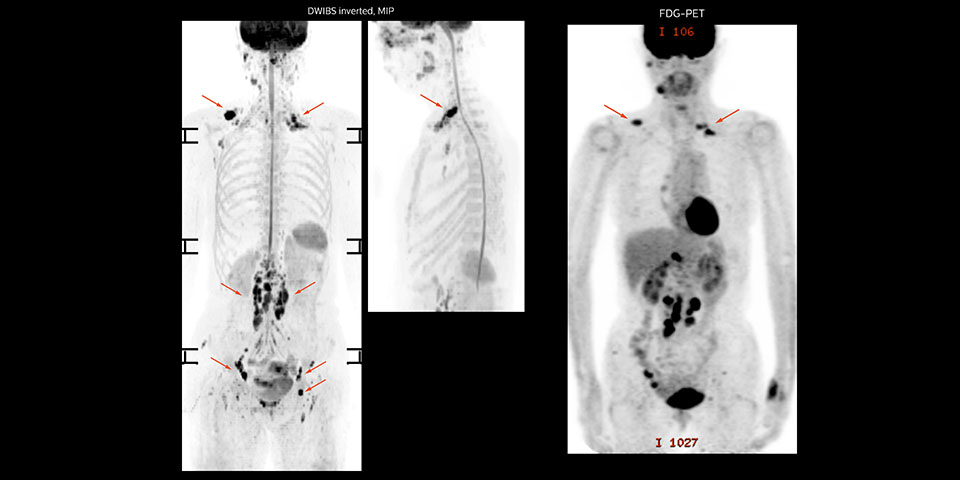

A 61-year-old female with a malignant lymphoma underwent an MRI exam with whole body diffusion weighted imaging (DWIBS) as well as PET. On the images shown, the resolution of DWIBS is better than PET, which allows visualization of the small pelvic lesions and almost no distortion is seen in the neck area.

Prodiva MRI whole body DWI lymphoma, Seirei Mikatahara

Prodiva MRI whole body FDG-PET, Seirei Mikatahara